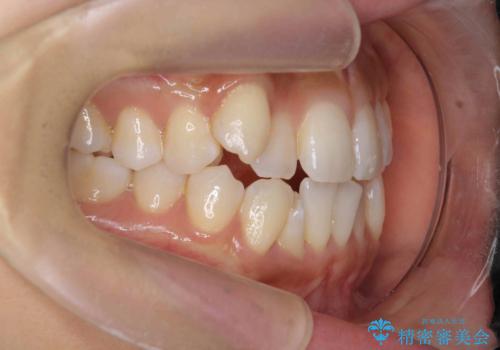

【審美装置】八重歯気になる

- 八重歯と叢生を主訴に来院されました。なるべく健康な歯を残したいという患者様の希望から、右側上下4番抜歯をしてワイヤー矯正する治療計画を立てました。

なるべく健康な歯を残したいという患者様の希望から、右側上下4番抜歯をして矯正しました。片側抜歯だったため、正中がズレないように気をつけながら治療を行いました。

正中もズレることなく主訴である八重歯と叢生を改善することができました。